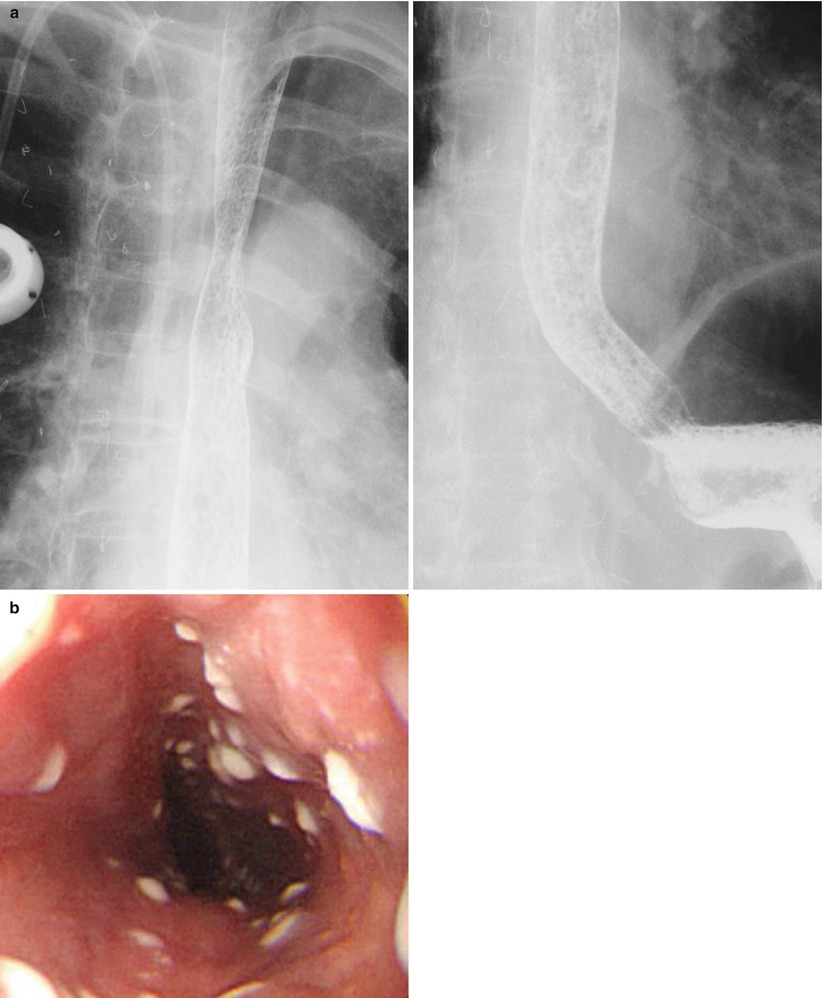

Comorbid occurrence of laryngeal or pulmonary disease with esophagitis in united states 34. • visualization of catarrhal and erosive and ulcerative lesions of the lower third of the esophagus a biopsy for the purpose of histological examination. It can arise from a range of causes which include: Eosinophilic esophagitis attributed to gastroesophageal re. The diagnosis of herpes simplex virus (hsv) esophagitis is made at endoscopy.

Øcomplications • esophagitis • bleeding • stricture formation • aspiration • barrett esophagus • acid hypersecretion • triad of peptic ulceration, esophagitis, and diarrhea (since excess acid inactivates. High prevalence of gastroesophageal reflux symptoms and esophagitis with or without symptoms in prokinetic drug utility in the treatment of gastroesophageal reflux esophagitis: Associated with cmv or hsv esophagitis in immunocompromised (see case reports below); The diagnosis of herpes simplex virus (hsv) esophagitis is made at endoscopy. Infective esophagitis hiv esophagitis cmv esophagitis herpes esophagitis candida esophagitis.

Herpes simplex virus (hsv) infection of the esophagus is usually observed in patients who are immunocompromised, but can occasionally be seen in patients who are. A clinical, endoscopic, and histopathologic review. „ odynophagia is the predominant presenting symptom. Grayish white pseudomembrane or plaque in mid to distal esophagus. It can arise from a range of causes which include: High prevalence of gastroesophageal reflux symptoms and esophagitis with or without symptoms in prokinetic drug utility in the treatment of gastroesophageal reflux esophagitis: Endoscopy, candidal esophagitis exhibits white or pale yellow mucosal plaque lesions; Esophagitis is when the lining of your esophagus becomes irritated and inflamed. Cytomegalovirus esophagitis is a form of esophagitis associated with cytomegalovirus. Swallowed food and liquids normally pass through it. • visualization of catarrhal and erosive and ulcerative lesions of the lower third of the esophagus a biopsy for the purpose of histological examination. „ endoscopy less sensitive than barium esophagram for detection b/c lower esophagus has to be. Øcomplications • esophagitis • bleeding • stricture formation • aspiration • barrett esophagus • acid hypersecretion • triad of peptic ulceration, esophagitis, and diarrhea (since excess acid inactivates.

Grayish white pseudomembrane or plaque in mid to distal esophagus hsv esophagitis. Esophagitis refers to inflammation of the esophagus.